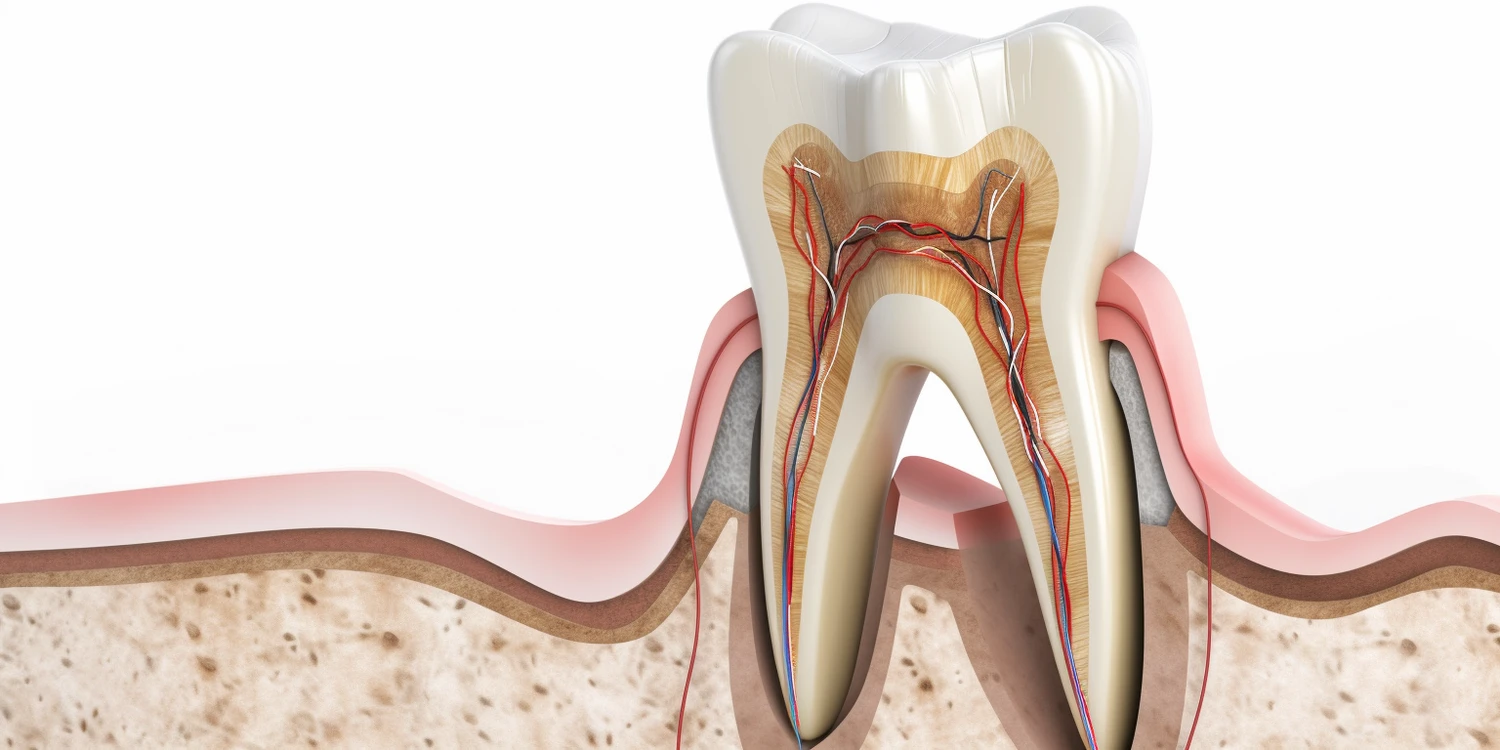

Leczenie kanałowe to skomplikowany proces medyczny, który ma na celu uratowanie zęba przed ekstrakcją poprzez usunięcie chorej miazgi oraz oczyszczenie kanałów korzeniowych. Proces ten zazwyczaj rozpoczyna się od dokładnej diagnostyki, która obejmuje zdjęcia rentgenowskie oraz badanie kliniczne mające na celu ocenę stanu zęba oraz otaczających tkanek. Następnie dentysta przystępuje do znieczulenia pacjenta, aby zapewnić mu komfort podczas zabiegu. Po znieczuleniu lekarz wykonuje otwarcie korony zęba, aby uzyskać dostęp do miazgi. Kolejnym krokiem jest usunięcie chorej miazgi oraz dokładne oczyszczenie kanałów korzeniowych za pomocą specjalistycznych narzędzi. Po oczyszczeniu kanały są dezynfekowane i wypełniane materiałem uszczelniającym, co ma na celu zapobieganie ponownemu zakażeniu. Na koniec dentysta zazwyczaj zakłada tymczasową lub stałą koronę na ząb, aby przywrócić mu funkcjonalność oraz estetykę.